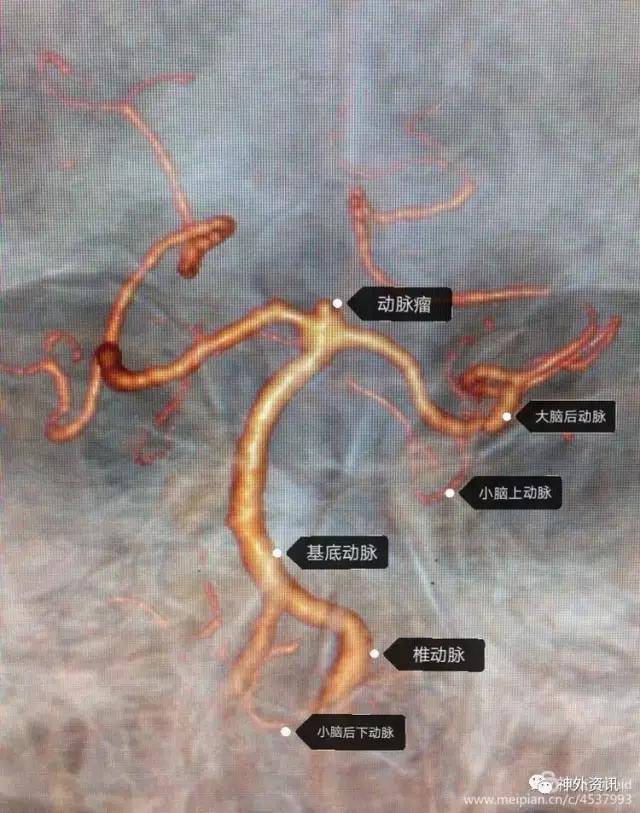

显示基底动脉尖动脉瘤和相关血管形态,可见动脉瘤窄蒂,瘤顶不规则,判断为责任病灶。双侧P1、P2血管形态正常。